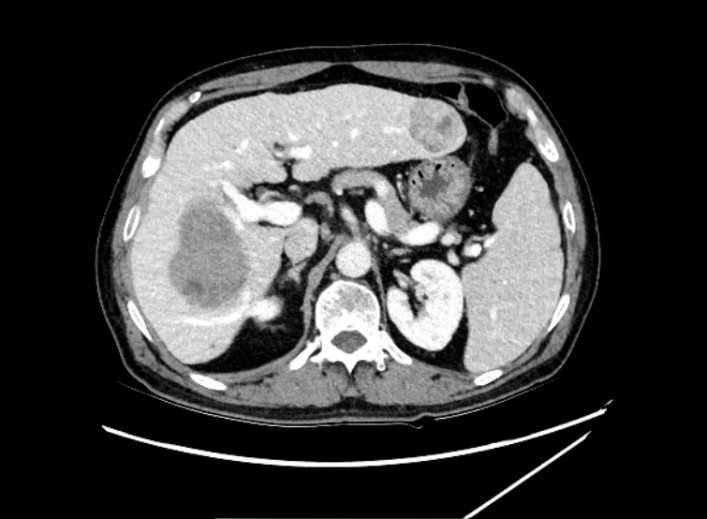

肿瘤体积超过半个肝 71岁的刘先生最近背部酸痛明显,活动受限,行走困难,就连晚上睡觉也只能趴着睡,但凡一扯到背部的肌肉,那种剧烈的疼痛让他直冒冷汗,连续贴了一个多月的膏药也无法有效缓解。 放心不下的他来到了浙江省人民医院越城院区就诊,医生为他做了胸片CT平扫后,发现他的肝脏部位隐隐约约有一个很大的肿块,建议做进一步的检查。 突如其来的噩耗让刘先生担忧不已,多方打听下,他慕名来到了肝胆胰外科、微创外科主任助理尚敏杰副主任医师处寻求帮助。 “经过磁共振等一系列检查,我们发现患者的右肝有个直径13公分的巨大恶性肿瘤,以及左肝也有一个鸡蛋大小肿块,两处肿瘤加起来,体积竟超过半个肝脏,甚至还有部分肿瘤已经累及横隔膜的可能。此外患者本身还有肝硬化、乙肝等疾病,治疗难度极大。” 术前左右肝可见占位 尚敏杰介绍,目前手术治疗是肝脏恶性肿瘤获得长期生存最重要的手段。好在患者肿瘤包膜完整,手术切除有价值,患者如果想要获得根治性切除,必须切除整个右侧半肝、左肝部分,以及部分膈肌,而根据三维成像技术电脑测算,切除所有肿瘤后,左侧半肝扣除左肝肿块后剩余肝体积不足45%,且患者有伴有慢性乙型肝炎肝硬化,属于极量肝切除。 术前拟保留肝脏体积标记计算 充分考虑后,刘先生最终还是选择了手术治疗。为了确保手术万无一失,肝胆胰外科、微创外科主任张成武主任医师与尚敏杰团队反复讨论手术方案、精心准备,最终在呼吸科、麻醉科、心血管内科等多个科室的大力配合下,手术顺利完成,肿瘤被完整切除,而且术中仅出血800毫升。术后患者出现一过性黄疸升高,进行了护肝治疗,并及时引流了在右胸腔内的反应性胸水,不久后患者整体体征逐渐趋于平稳,平安出院了。 术后复查残余部分左肝 3D成像软件精准评估 可耐受极量肝切除体积 肝脏可以切掉一部分吗? 肝脏是一个非常重要的器官,是人体代谢的中心,主要功能是分泌胆汁,参与蛋白质、脂肪、糖类的代谢,另外还有着解毒、凝血和造血的功能。一般情况下,正常的肝脏可以切掉一部分,只要残余体积不小于30%,肝细胞就可以代偿正常人体所需要的各种功能。 张成武介绍,肝脏切除后,剩余的肝脏会肥大再生,恢复到原来的体积,以适应机体的各种功能。 但是…… 如果患者本身肝脏有慢性肝炎、肝硬化等基础疾病,可能会导致肝脏的再生能力会减弱,恢复时间较久,一般手术后残余肝脏体积不能小于40%,如果切除体积超过此界限后,患者可能会出现肝脏功能不全甚至肝功能衰竭的风险,死亡率较高。 “一般来说,手术前我们往往都会评估患者肝脏的储备功能,通过CT图片用3D成像软件标记剩余的肝脏,计算剩余肝脏与标准肝体积的比值,来评估肝脏是否耐受极量肝切除体积。” 患者在肝脏切除手术后,肝脏合成蛋白的能力降低,因此补充优质蛋白非常必要,建议少量多餐,多吃含有优质蛋白的食物如鱼、虾、蛋、奶、瘦肉等。另外可以多吃些新鲜的蔬菜和水果,及时补充维生素,增强身体免疫力。避免过度劳累、熬夜。 肝胆胰外科、微创外科 浙江省人民医院肝胆胰外科、微创外科是浙江省医学重点学科(支撑学科)、浙江省重点学科群(微创外科学科群)核心科室,医院重中之重学科。以肝胆胰疾病微创手术治疗为特色,80%以上为微创手术,年均腹腔镜肝胆胰肿瘤手术超过500例,开展腹腔镜肝门部胆管癌根治性切除、腹腔镜胆囊癌根治术、腹腔镜巨大肝癌切除、腹腔镜二步肝切除、腹腔镜保留十二指肠的全胰切除、腹腔镜RAMPS手术等高精尖手术。另外,科室开展的腔镜减重和腔镜胃食管反流病等特色手术量居省内前三,综合实力居国内领先水平。